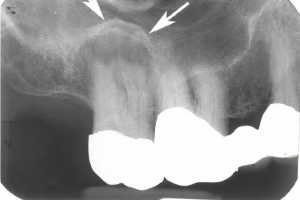

Радиационно-индуцированный некроз или остеорадионекроз характеризуется наличием обнаженной кости после проведения лучевой терапии. Открытая кость может полностью секвестрировать, что часто приводит к обнажению большего количества кости. Хотя кость, расположенная в любом месте челюсти, восприимчива к излучению, задняя часть нижней челюсти поражается чаще, чем другие области, потому что она часто находится в поле излучения, особенно когда в лечение включены лимфатические узлы. Может возникать интенсивная боль при периодическом отеке и дренировании вне полости рта. Однако многие пациенты не чувствуют боли при обнажении костей. Утрата нормальной структуры может нарушить целостность кости, а в некоторых случаях кость может сломаться.